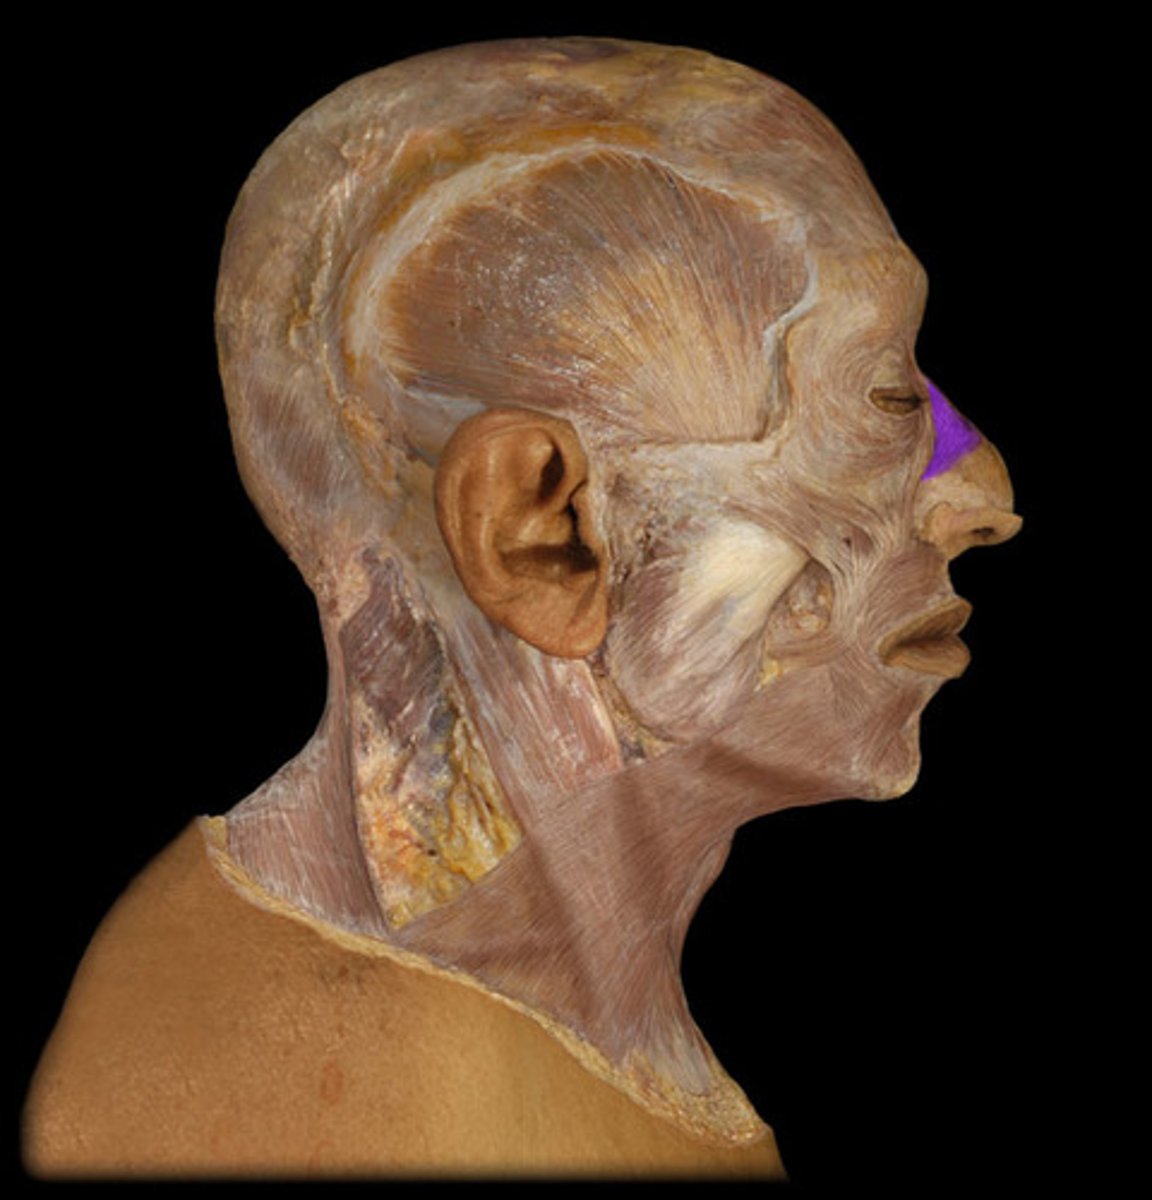

Orbicularis oculi